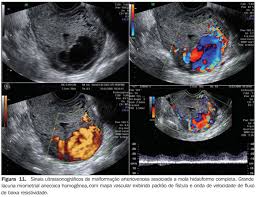

Anormalidades Do Primeiro Trimestre Da Gravidez Ensaio Iconografico